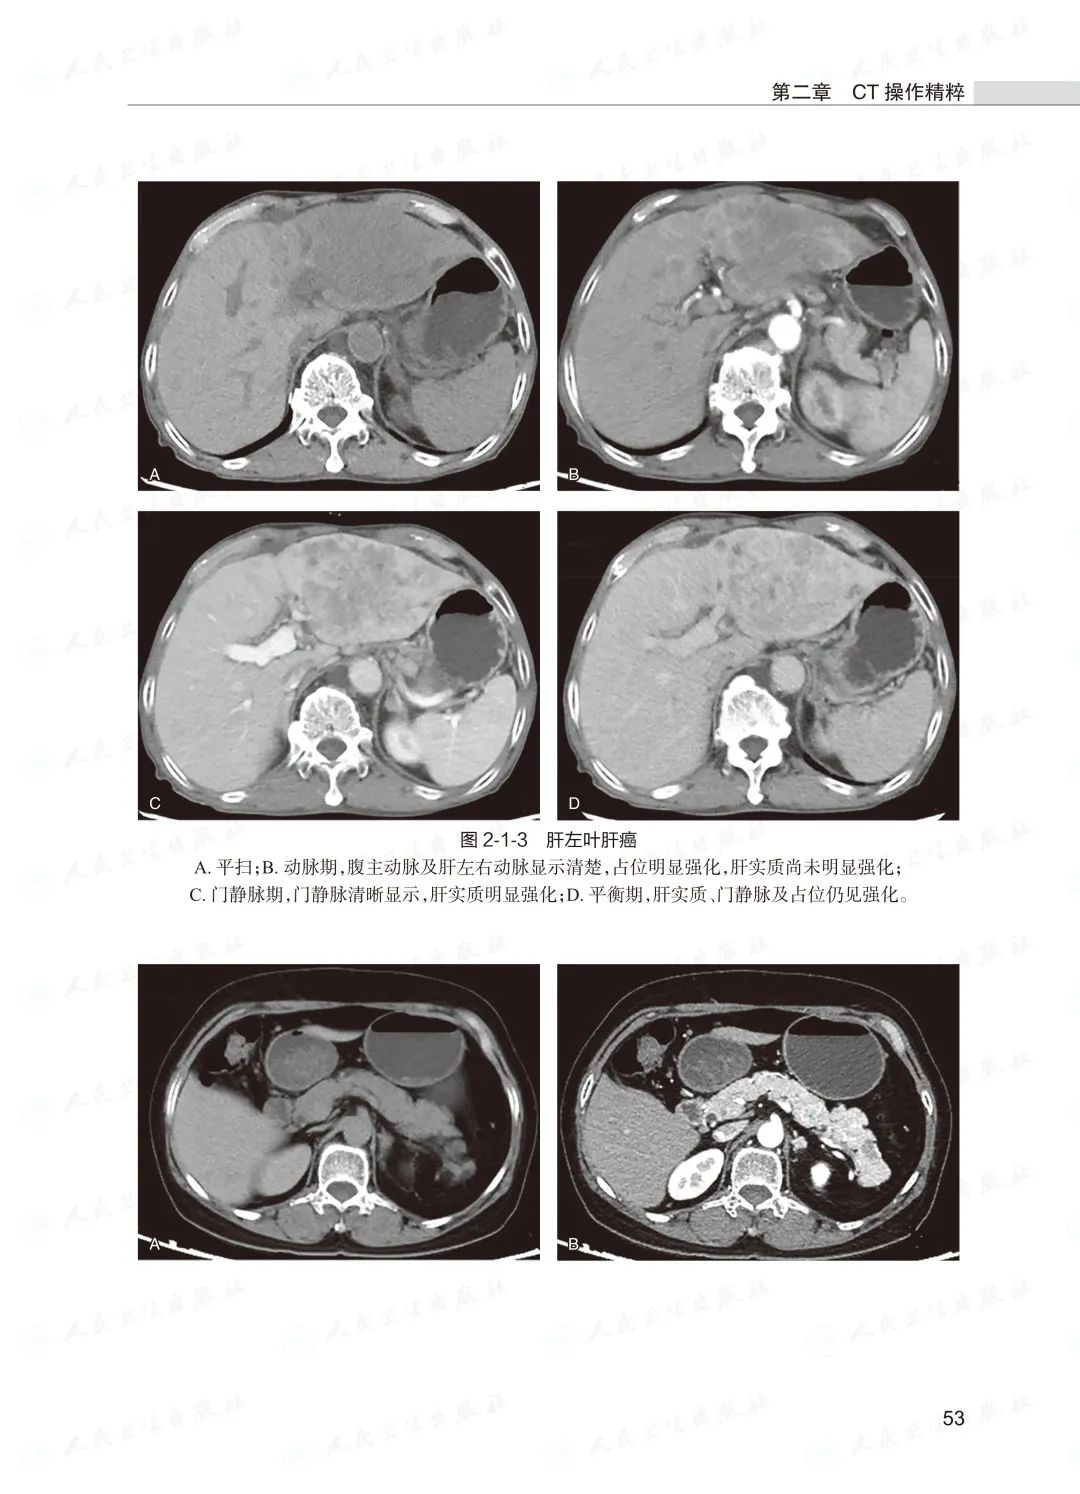

本书图文并茂,并配有8个高清视频内容,将为从事医学影像诊断和介入诊疗的医生提供临床技能培训。

☆ 对于影像诊断,重点介绍各种影像检查技术的适应证、禁忌证及检查前准备、检查关键技术、图像后处理和解读等,尤其是新技术的原理、操作规范等。